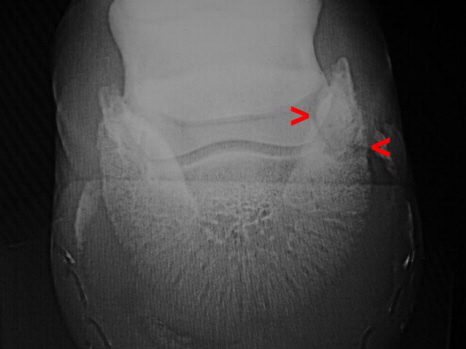

Hufbeinastraktur